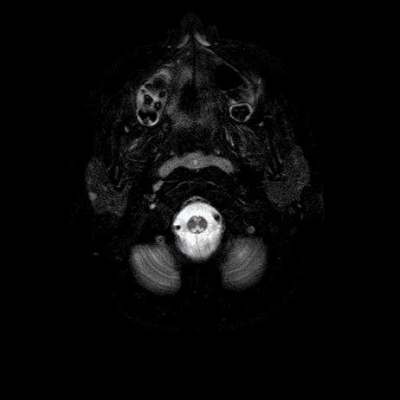

- A) Aksiyel T2A ve koronal T2A sekanslarda sentrum semiovale, korona radiata ve bazal ganglionlar düzeyinde bilateral frontoparietal derin periventriküler beyaz cevherde birleşme eğilimi gösteren hiperintens gliotik sinyal değişiklikleri (oklar) ve aksiyel T2A serilerde servikal spinal kordda posterior kolonda, lateral kesimlerde sinyal artımları (oklar) izlendi.

- LBSL, karakteristik radyolojik özelliklere sahiptir. MRG’de tipik olarak bilateral ve simetrik beyaz cevher sinyal değişiklikleri görülürken, subkortikal U lifleri, internal kapsülün posterior kolları, trigeminal sinir traktları, serebellum, korpus kallozumun spleniumu, medulla oblongata ve omurilikteki dorsal kolonlar ile lateral kortikospinal traktlar genellikle korunur.

- Etkilenen bölgelerde T1’de hipointens, T2/FLAIR’da hiperintens sinyal değişiklikleri izlenir. DWI’de lezyonların periferinde kısıtlı difüzyon görülebilir. MRS’de beyaz cevherde laktat artışı saptanabilir, ancak bu her hastada mevcut değildir.

- LBSL tanısında majör kriterler; subkortikal U lifleri korunmuş serebral beyaz cevher, servikal düzey dahil omurilik dorsal kolonları ve lateral kortikospinal traktlar, medulla oblongata piramitleri veya medial lemniskus dekusasyonu tutulumu iken; minör kriterler korpus kallozum spleniumu, internal kapsül posterior kolu, superior ve inferior serebellar pedinküller, trigeminal sinir traktları, mezensefalik trigeminal yollar, medulla oblongata anterior spinosebellar traktları ve serebellar beyaz cevherdeki sinyal değişiklikleridir.